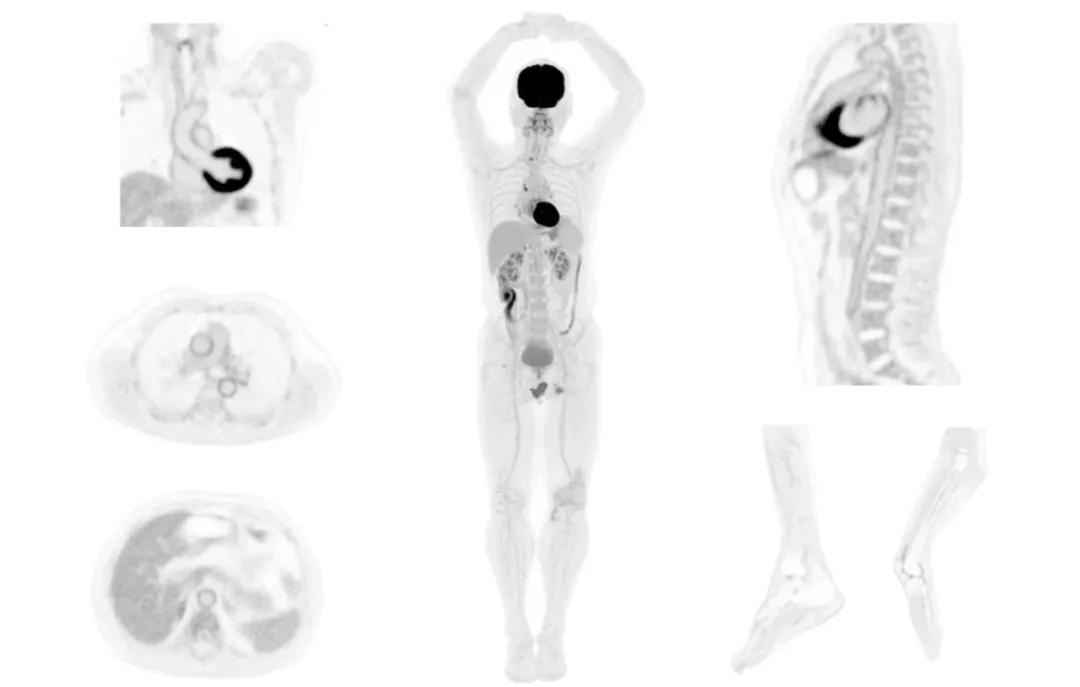

只有国内的医疗企业拥有了自主核心研发技术,才能在与国外的行业龙头公司竞争中脱颖而出,在质量和价格保证的前提下,利用价格优势才可以快速转变国内行情,占领国际市场。2016年明峰医疗有限公司自主研发的PET\CT获得中华人民共和国医疗器械注册证,标志着我国的大型高端医疗影像设备研制与生产打破了国内同类产品以进口为主的现状,迈向了一个新阶段。2017年由加利福尼亚戴维斯分校、宾夕法尼亚大学以及劳伦伯克利国家实验室的顶级分子影像专家们发起的全景扫描PET-CT“探索者”项目,将实时动态全身人体扫描的构想变为现实,被行业戏称为遥望人体的“哈勃望远镜”。传统的PET/CT轴向视野最长不超过30cm,但是“探索者”即将将其拓展到2m,因此其于传统设备灵敏度相比可高达至其40倍左右。此项目中研发的实时全身动态扫描技术可以精准呈现人体内动态代谢过程。而此项将改变分子影像领域的项目宣布其全球唯一研发与产业化的合作伙伴则是联影公司。

注射总剂量为7.8mCi,14分钟全身采集时间,在拥有超高灵敏度与超高分辨率的uEXPLORER上,即可得到展示显示人体诸多精细结构的高清三维图像。